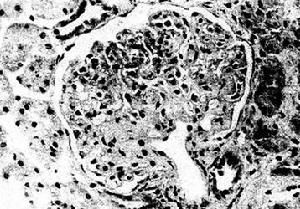

成人膜性腎炎蛋白尿在小管間質腎病-葡萄膜炎綜合徵患者,發熱亦常見。臨床表現除持續性腎功能和小管功能損害骨髓和淋巴肉芽腫外,還在病程某一時刻出現葡萄膜炎部分病例可發生骨髓肉芽腫。腎活檢病理檢查可見間質浸潤淋巴細胞、漿細胞嗜酸粒細胞,系膜免疫球蛋白沉澱小管顆粒狀IgE和C3沉澱。根據以上特點可作出診斷。

其它輔助檢查:腎活檢病理檢查可見間質浸潤淋巴細胞、漿細胞嗜酸粒細胞系膜免疫球蛋白沉澱,小管顆粒狀IgE和C3沉澱。